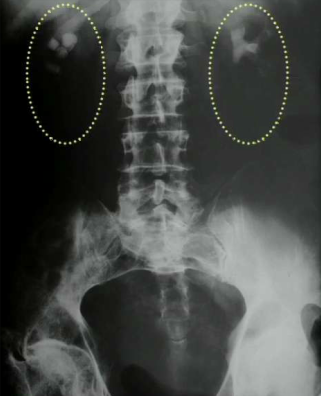

What does this patient have?

Ascities. Note increased density, central bowel loops, thickened peritoneal fat stripe, loss of other edges (liver, spleen and bladder)